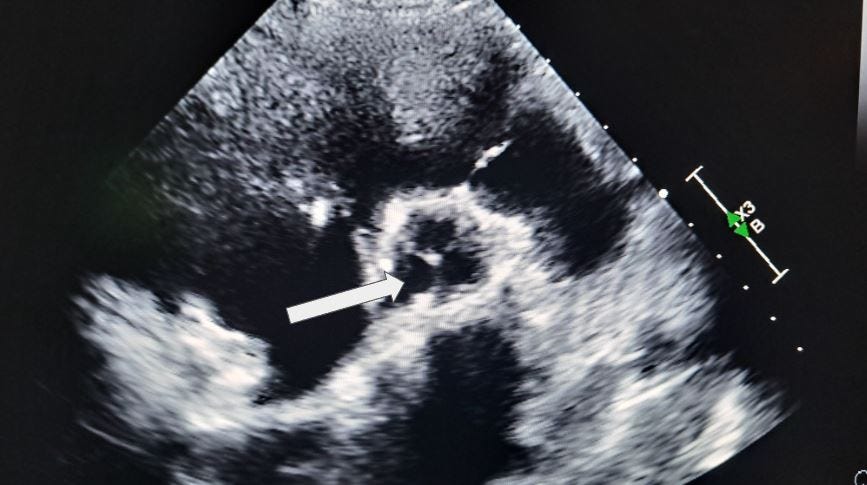

What section of the aorta is the arrow pointing to in this 3-chamber view?

A. Aortic Root

B. Descending aorta

C. Abdominal aorta

D. Aortic Arch